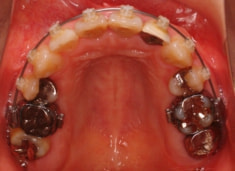

右下7番欠如歯(保存不可能歯につき抜歯)右下8番利用

治療法:フルパッシブブラケット:クリアスナップ

治療開始から1年8ヶ月後